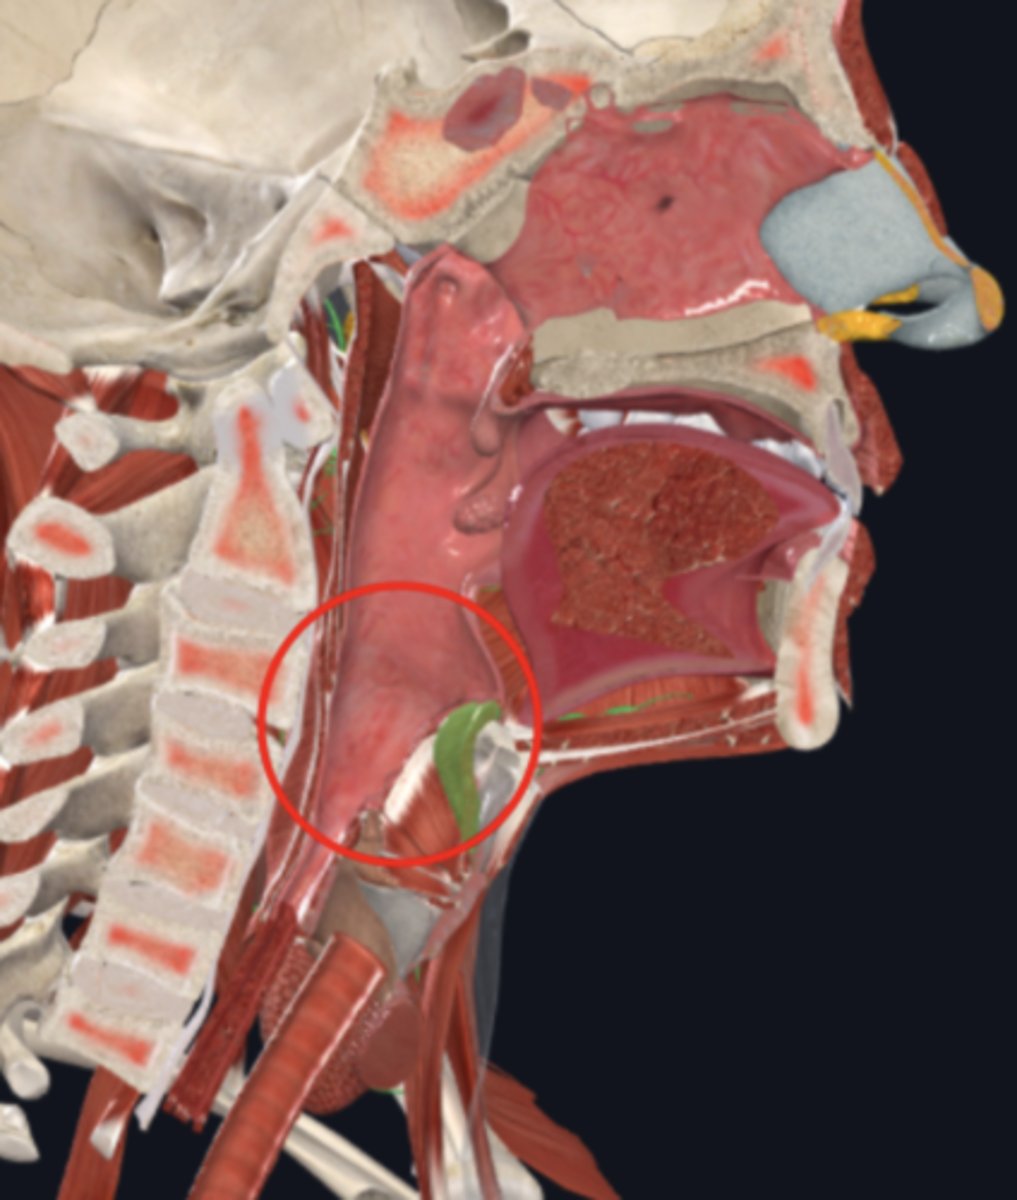

nasopharynx

name the circled region

oropharynx

name the circled region

laryngopharynx

name the circled region